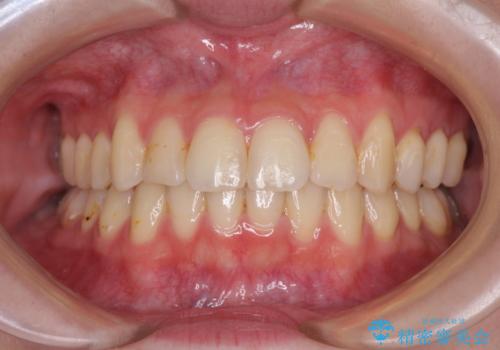

顎が左右にずれた咬み合わせ ハーフリンガルの抜歯矯正

裏側装置での交叉咬合改善は非常に困難なもので、頻繁に装置の脱落がありました。

それでも想定以上に治療期間は長期化せず、咬み合わせも口元も満足のいく仕上がりとなりました。